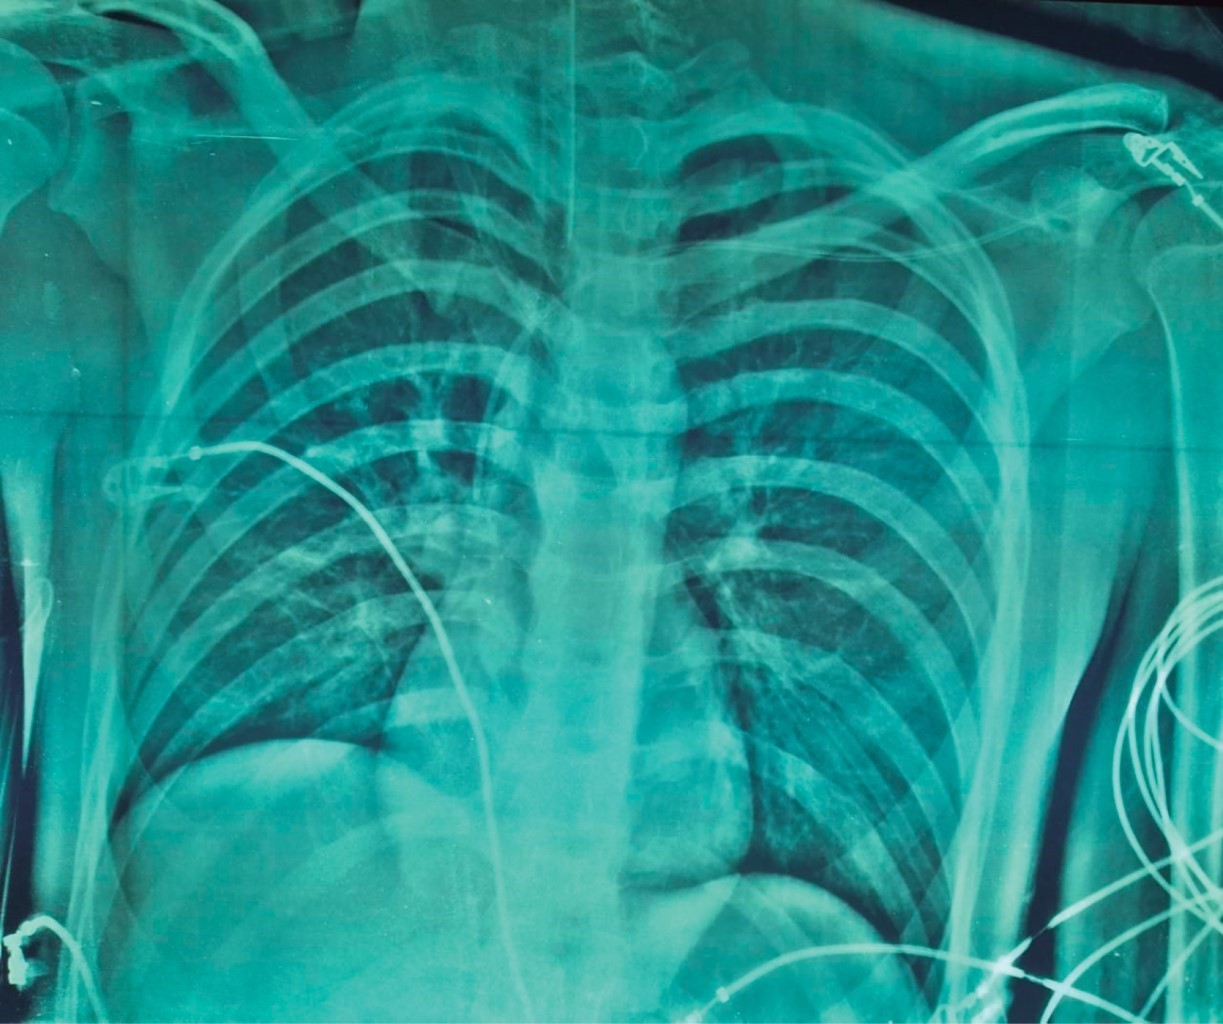

Se presenta el caso de masculino de 16 años de edad que ingresa con diagnóstico de herida por arma de fuego en cráneo, para su evaluación por el Servicio de Neurocirugía, quien establece la muerte encefálica por clínica corroborada por estudio de angiotomografía (Figura 1), donde se aprecia ausencia de flujo arterial cerebral, avisando a la Coordinación de Donación de Órganos y Tejidos con fines de trasplante. Sin antecedentes de importancia, síntomas ni vacunación previa para COVID-19. Se aborda a familiares para solicitar la donación de órganos; la madre, ya que un año previo había fallecido el padre, acepta que se inicie el proceso. Se realizó protocolo de ingreso con laboratorios (Tabla 1) y estudios de gabinete, además de colocación de catéter venoso central; se realiza telerradiografía de tórax sin evidencia que sugiera lesiones o patología pulmonar (Figura 2). La prueba de reacción en cadena de la polimerasa con transcriptasa inversa (PCR-RT) para SARS-CoV-2 se realizó vía nasofaríngea y se envió al Laboratorio Estatal de Salud Pública de nuestro estado quien realiza el procesamiento de estas muestras. Al mismo tiempo se realizaron estudios de laboratorio para evaluar los órganos y tejidos viables para trasplantes siendo el corazón, hígado, ambos riñones, ambas córneas y tejido musculoesquelético. Sin embargo, al ser donante pediátrico grupo y Rh sanguíneo B+, se contactó al Centro Nacional de Trasplantes (CENATRA) para la búsqueda de receptores, cabe mencionar que no hubo receptores para el órgano cardiaco. Un centro hospitalario refirió tener receptor de hígado con urgencia de trasplante, dos centros refirieron tener un receptor pediátrico cada uno para los riñones, otro centro aceptó tener receptores de córneas y un banco de tejidos aceptó participar en la extracción del tejido musculoesquelético.

Figura 2